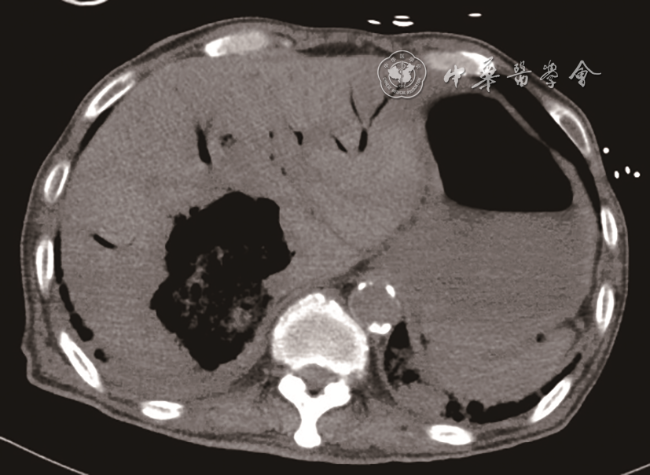

入急诊科时患者血压为60/29 mmHg(1 mmHg=0.133 kPa),心率为143次/min,末梢氧饱和度低,气管插管呼吸机辅助通气。11月26日急诊床旁超声检查提示:肝内多发高回声包块并肝静脉内气体样强回声漂动入下腔静脉、右心,肺动脉内可见大量气体样强回声,考虑产气型肝脓肿破裂(图12动态图1)。急诊平扫CT检查提示:肝多发类圆形混杂气体密度灶,肝内外胆管扩张、积气(图3)。当日血培养检出高黏性肺炎克雷伯菌(Klebsiella pneumoniae,KP),菌拉丝阳性,毒理强。血常规检查结果如下:快速C反应蛋白:243.18 mg/L(正常值范围≤10.00 mg/L);白细胞:15.93×109/L[正常值范围(3.50~9.50)×109/L];中性粒细胞百分比:93.5%(正常值范围40.0%~75.0%);血糖:38.7 mmol/L(参考值3.9~6.1 mmol/L);谷草转氨酶:247 U/L(参考值15~40 U/L);碱性磷酸酶:369 U/L(参考值45~125 U/L);谷氨酰基转移酶:349 U/L(参考值10~60 U/L);血肌酐:195 μmol/L(参考值59~104 μmol/L);尿酸:772 μmol/L(参考值208~428 μmol/L);尿常规:葡萄糖(++++)(正常值:阴性);血白介素6:2887.00 pg/ml(正常值范围0.00~7.00 pg/ml)。

图2 超声声像图示右心房内大量“气体样”强回声

临床对于脓肿自发破裂的诊断相对困难。脓肿破裂情况下患者病情往往危重,不适宜行CT检查,床旁超声检查则成为首选。产气型肝脓肿的超声表现以脓腔内片状强回声或肝内胆管系统积气多见9。Pham等10报道1例肝脓肿破裂引起气腹及腹膜炎的病例,术前超声、CT检查均未确诊,后通过剖腹探查确诊。既往报道了1例肝脓肿破裂引起肝静脉积气的患者,超声能实时、快速地观察肝静脉内气体动态变化,这为肝脓肿破裂的诊断提供了有力证据,从而为临床治疗提供更好的指导11。超声可以观察到肝静脉内气泡的有节律的与心率相关的运动,可用于区分气泡是位于门静脉系统、肝内胆管还是位于肝静脉系统12。本病例中CT检查同样发现肝内积气,但将肝静脉内积气误认为了肝内胆管积气。本病例超声显示肝静脉内大量气泡有节律地向下腔静脉内漂动,气泡再通过下腔静脉漂动至右心、肺动脉。这种表现提示血行播散,或可为KP肝脓肿的肝外血行播散,如眼内炎、中枢神经系统感染、坏死性筋膜炎等的诊断提供线索。